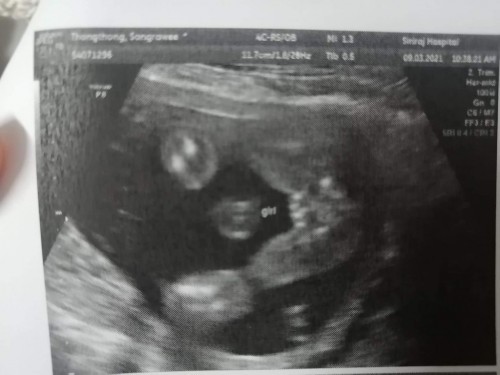

พอดีเราซาวด์ตอนแรกกับนักศึกษาแพทย์เขาบอกว่าน้องเป็น ผช. พออาจารย์หมอตรวจซ้ำบอกน้องเป็น ผญ. แต่คนรู้จักทักหมดเลยเหมือนได้ลูก ผช.ผิวคล้ำขึ้น ไม่ค่อยออร่าค่ะ

กี่วีคแล้วคะ ผิวดำไม่เกี่ยวหรอกค่ะ ตอนเราท้องแรกผญก็สิวเยอะดำ ใกล้ๆคลอดถึงจะขาวค่ะ อันนี้รูปเด็กผชค่ะ ของเราท้องสอง

ดูเป็นกลีบอยู่นะคะ แต่ดูอีกทีก็เหมือนจู๋เลย รอหมอคอนเฟิร์มอีกรอบนะแม่ 😂